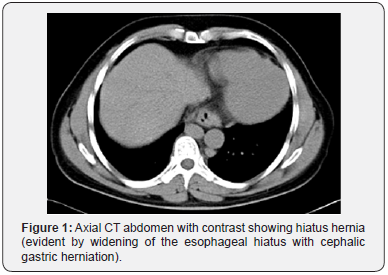

His general investigations (full blood count, random blood glucose, renal and liver profiles) were within normal ranges. His CXR showed normal lungs, levocardia and a right-sided gastric bubble. ECG revealed no abnormalities. A trans-thoracic echocardiography was normal apart from unusual drainage of hepatic veins directly into the right atrium. A multi-detector CT (MDCT) scan of the abdomen (with oral and intravenous contrast) confirmed the hiatus hernia (Figure 1) and revealed a right-sided stomach, a two-humped left-sided liver (Figure 2), polysplenia (three splenic masses, two on the left beneath the liver and one on the right) (Figure 3), a pre-pancreatic portal vein (Figure 4) and an absent inferior vena cava (IVC) with a direct continuation of azygous and hemi-azygous veins (Figure 5). Therefore, CT findings were consistent with heterotaxy syndrome with a left isomerism (polysplenia syndrome).